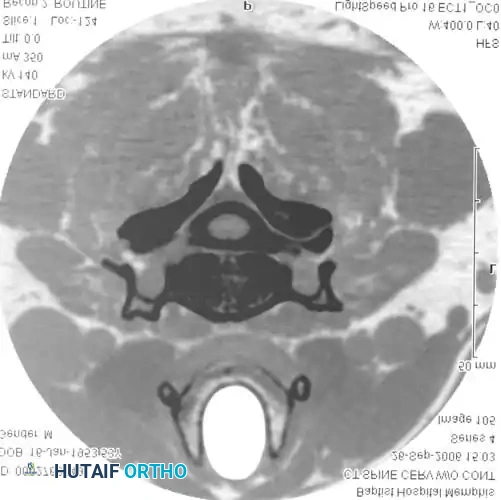

DIAGNOSTIC STUDIES Surgical Diagram

Fig. 39-6 A: MRI Sagittal view of a 45-year-old patient with right C7 radiculopathy. The MRI was inconclusive for a definitive disc herniation.

Fig. 39-6 B: MRI Axial view of the same patient, failing to clearly delineate the intraforaminal pathology.